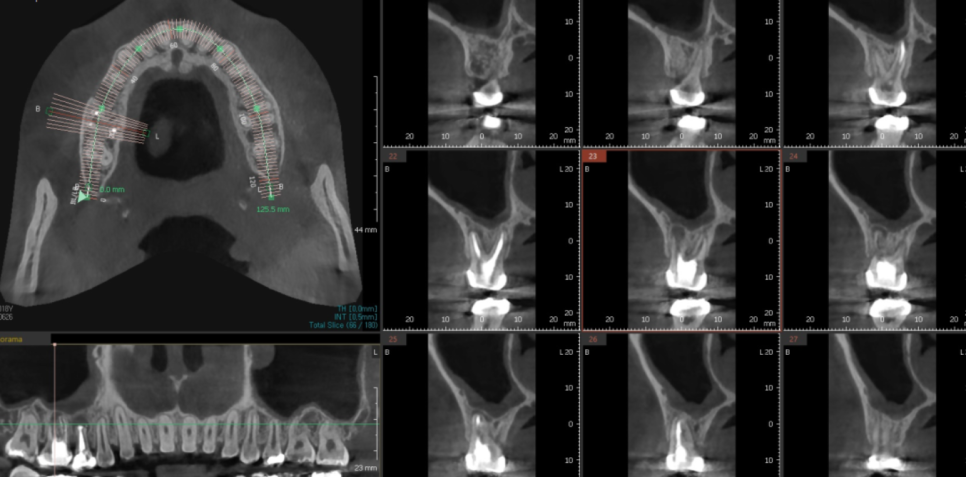

ct를 한번 찍어보았습니다.

23.06.26

ct상에서는 치아로부터 시작한 염증이

상악동까지 번진 모습이었습니다.